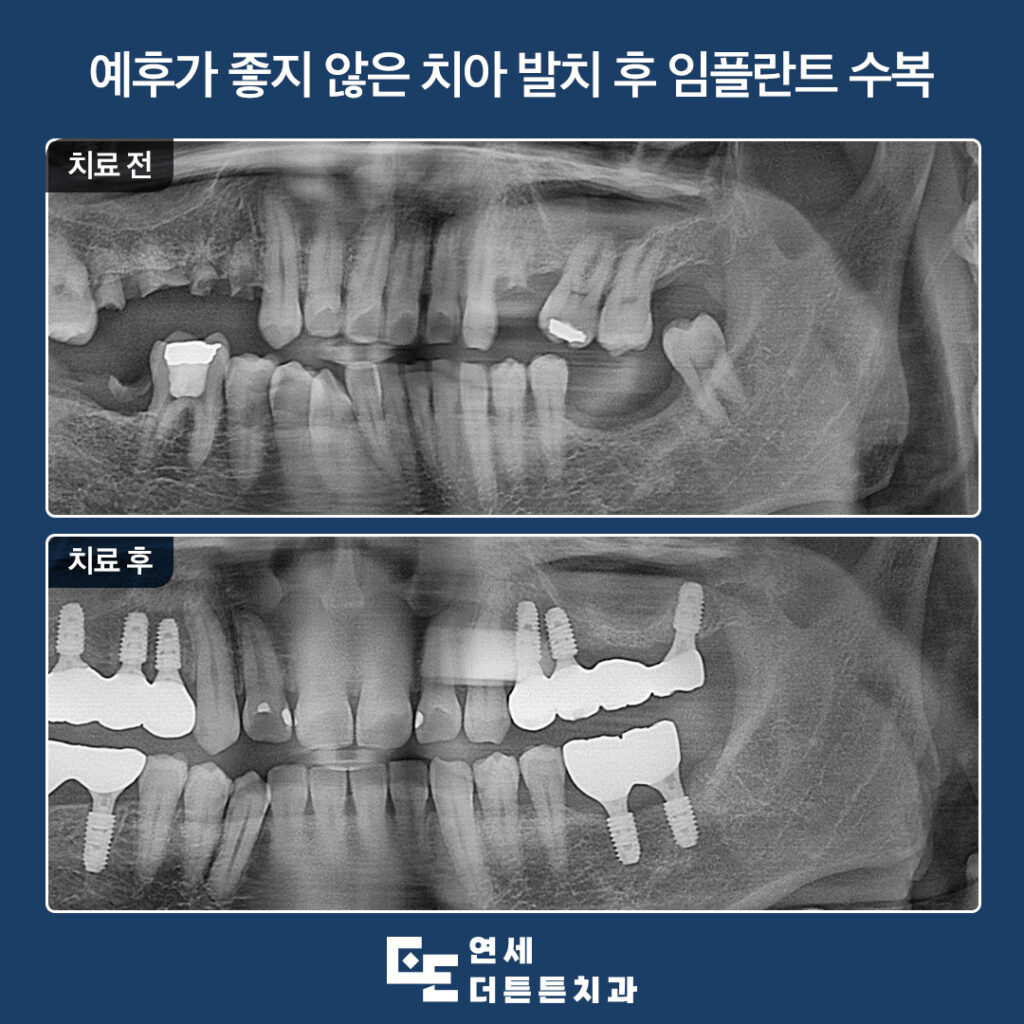

오늘은 예후가 좋지 않은 치아들을 발치하고

어금니 부위 방학역치과 임플란트를 진행하신

환자분을 소개해 드리도록 하겠습니다.

환자분께서는 치아가 부러진 것도 많고

어금니가 없어서 식사가 힘드시다며

치료를 시작하기 위해 내원해 주셨습니다.

치아가 부러져 뿌리만 남아 있거나

어금니를 상실하신지 오래되어 치아가 앞쪽으로

치우쳐져 살려 쓰기 힘든 치아들은 발치 후

임플란트 식립을 통해 기능을 회복할 수 있도록

계획을 수립하였습니다.

안정적으로 최종 보철물까지 수복한

모습입니다.